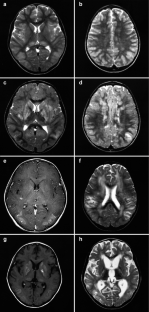

We document the MRI features in six patients aged 5–14 years with acute encephalitis following measles. The diagnosis was made on a characteristic morbiliform rash and detection of specific IgM and IgG antibodies. The symptoms of encephalitis occurred 1–11 days after the appearance of the rash. All patients underwent MRI within 1–4 days of the onset of neurological symptoms. Diffusion weighted images (DWI) were obtained in three patients. In all patients, T2-weighted images showed widely distributed, multifocal high signal in both cerebral hemispheres with swelling of the cortex, with bilateral, symmetrical involvement of the putamen and caudate nucleus. The lesions had showed low apparent diffusion coefficients. Three patients showed subacute gyriform haemorrhage, and asymmetrical gyriform contrast enhancement on follow-up MRI.

Fig. 1a-h.